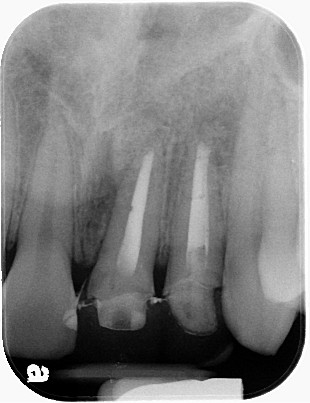

利用顯微鏡將金屬釘柱移除,再以鎳鈦超彈性器械修形根管(圖三),待患者的症狀都恢復正常後再利用熱塑型馬來膠將根管緻密封填(圖四),圖五為根管治療後的情況,與圖二相比,可見正門齒及側門齒已徹底封填。

圖十四為手術後的X光片,可見根尖逆充填及根尖囊腫,都已完全處理,經過6個月後,牙根的破壞已完全癒合(圖十五),可繼續進行瓷牙重建。